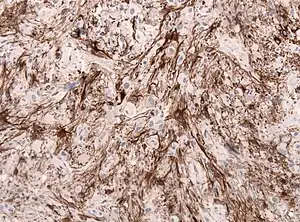

| GFAP stained microscopic section of a subependymal giant cell astrocytoma | |